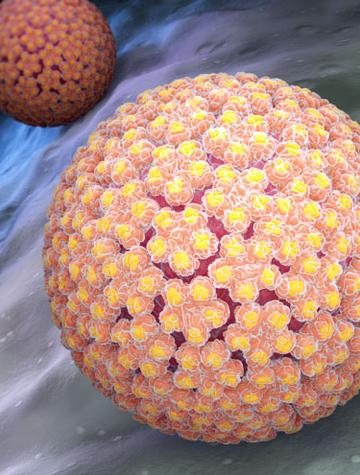

Cancers de l’oropharynx et papillomavirus oncogènes

Les papillomavirus oncogènes sont responsables d’une part croissante de cancers oropharyngés (COP). La prévalence de ces cancers est particulièrement élevée en Amérique du Nord et en Scandinavie où 60 à 80 % des COP sont causés par les papillomavirus oncogènes(1,2). En France, d’après plusieurs études récentes 30 à 40 % des COP sont attribués aux papillomavirus et leur incidence est vraisemblablement en augmentation(3)